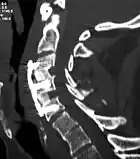

CT scan of a patient after 2-level anterior cervical discectomy & fusion (ACDF) with allograft.

The surgery requires a short stay in the clinic (1 to 3 days) and a gradual recovery between 1 and 6 weeks. However, the technology has advanced and it can be performed by 'Endoscopic Micro Discectomy" with the patient able to continue their normal life in two days. The patient may be advised to wear a neck brace or collar (for up to 8 weeks) that serves to ensure proper spinal alignment. Wearing the brace heightens one's awareness of posture and positioning and helps prevent movements (e.g., sudden and/or excessive bending or twisting of the neck) that may aggravate or slow down the healing process.